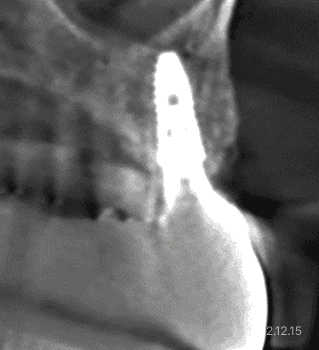

뼈이식 전 CT단면

뼈이식 전

CT단면

노출형 뼈이식 후 CT 단면

뼈이식 최종 완성 후 CT 단면